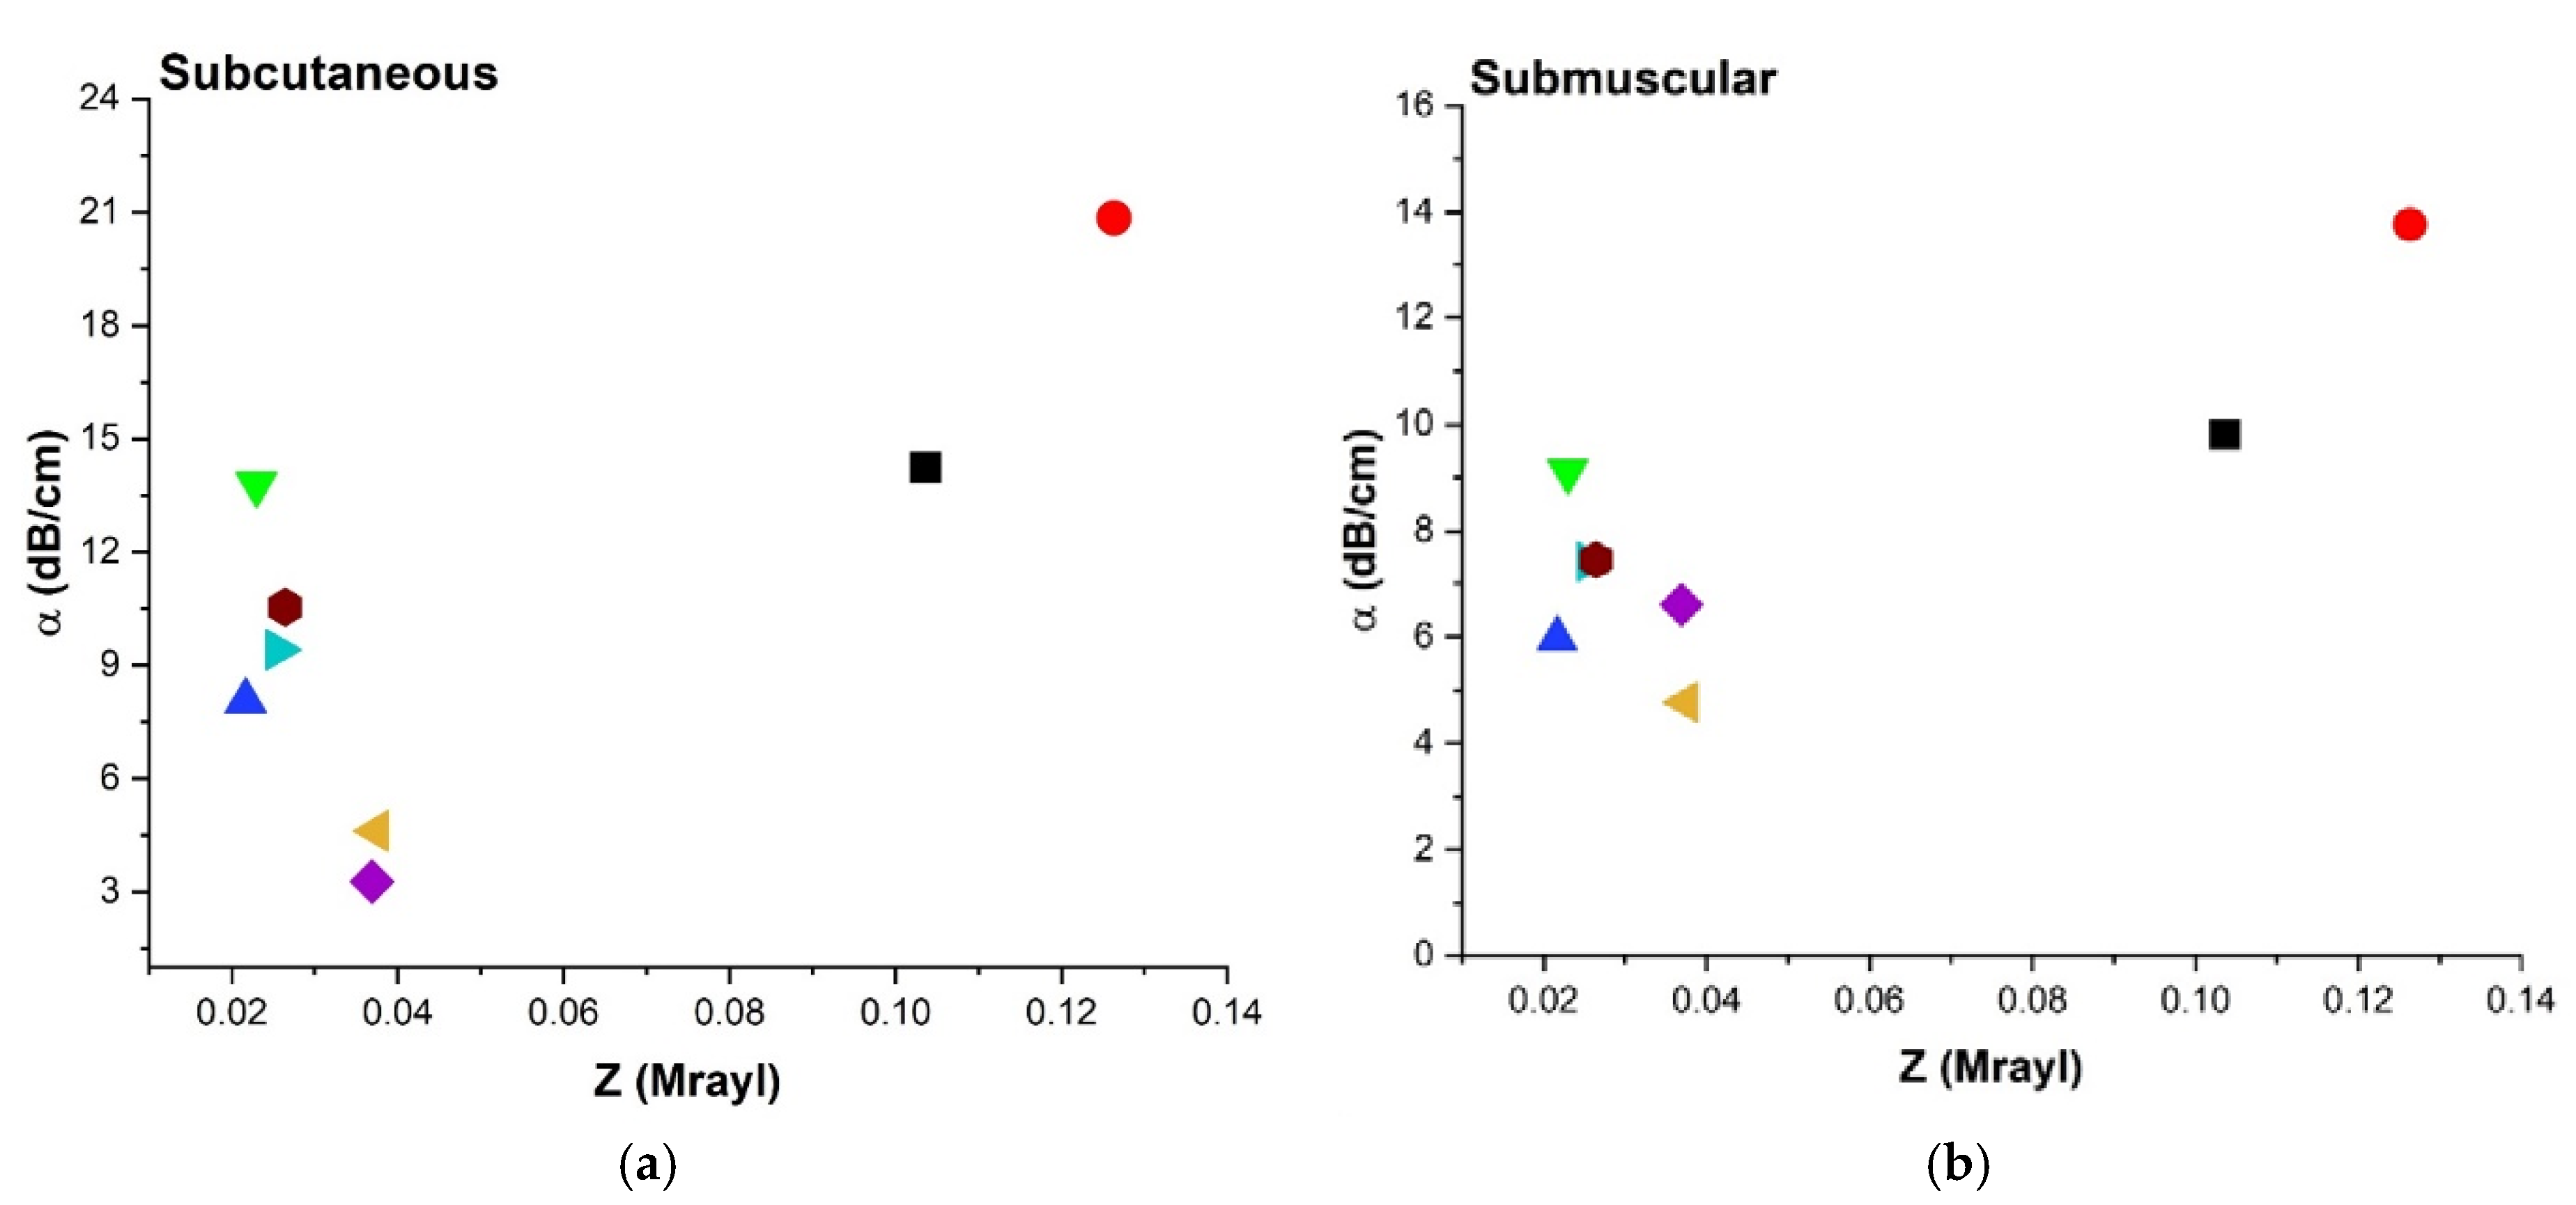

3.4.5. Acoustic Impedance (Z) and Attenuation Coefficient (α)

4.3.4. Attenuation Coefficient (α), Impedance

| Aerogel | Aq Attenuation α (dB/cm) | SM Attenuation α (dB/cm) | SC Attenuation α (dB/cm) |

|---|---|---|---|

| X-silica-La2O2S:Eu | 8.21 ± 0.14 | 13.76 ± 1.15 | 20.84 ± 0.14 |

| X-silica | 7.13 ± 0.15 | 9.80 ± 0.38 | 14.24 ± 0.98 |

| SMPU-Mix-18 | 6.53 ± 0.01 | 9.12 ± 0.17 | 13.80 ± 0.07 |

| SMPU-Mix-14 | 4.30 ± 0.88 | 5.96 ± 0.55 | 8.06 ± 0.70 |

| X-Ca-Alg-2 | 3.54 ± 0.09 | 7.46 ± 0.39 | 10.54 ± 0.08 |

| X-Ca-Alg-1 | 3.11 ± 0.12 | 7.42 ± 0.21 | 9.41 ± 0.35 |

| BRF-CA | 2.68 ± 0.35 | 6.60 ± 0.67 | 4.61 ± 0.16 |

| ARF-CA | 2.39 ± 0.44 | 4.77 ± 0.46 | 3.27 ± 0.05 |